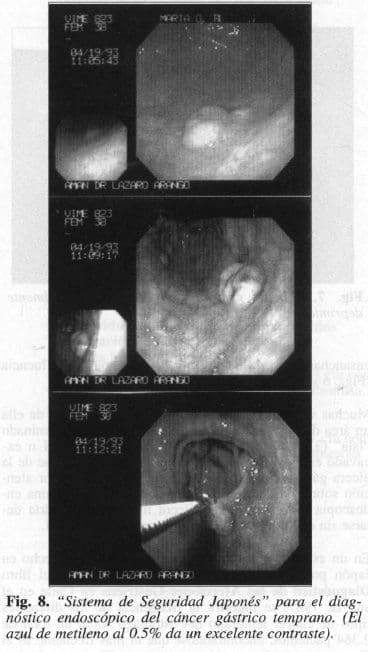

Por lo tanto, la endoscopia es de vital importancia para el diagnóstico del cáncer temprano. La metodología propuesta por Kiyonari (30), habla del Sistema de Seguridad Japonés el cual consta de varios niveles:

1. Toda lesión sospechosa debe ser fotografiada, para sacar una conclusión.

2. Luego, debe ser coloreada y nuevamente fotografiada y así sacar otra conclusión (Fig. 8).

3. Luego, debe ser biopsiada’y así sacar una nueva conclusión. Con lo anterior debe darse un margen de seguridad de un 98% para el diagnóstico del cáncer gástrico (30).

Con la endoscopia podemos realizar coloraciones que nos permiten visualizar por medio de un mejor contraste lesiones pequeñas hasta de 2 mm, que de otra forma sería difícil detectarlas. Estas coloraciones han sido utilizadas en muchos órganos; en el estómago los primeros en usarlas fueron Tsuda y Aoki. Las soluciones utilizadas son el azul de metileno al 0.5%, el azul de Evans al 1% Y el Indigo Carmín. En nuestro hospital y por mayor disponibilidad y bajo precio usamos el primero, que llena los requisitos de ser de fácil disolución, sin efectos colaterales, proporciona excelente contraste y no altera el área lesionada. Con lo anterior hemos podido estudiar en forma detenida muchas lesiones y ha aumentado en forma importante el número de lesiones tumorales encontradas.